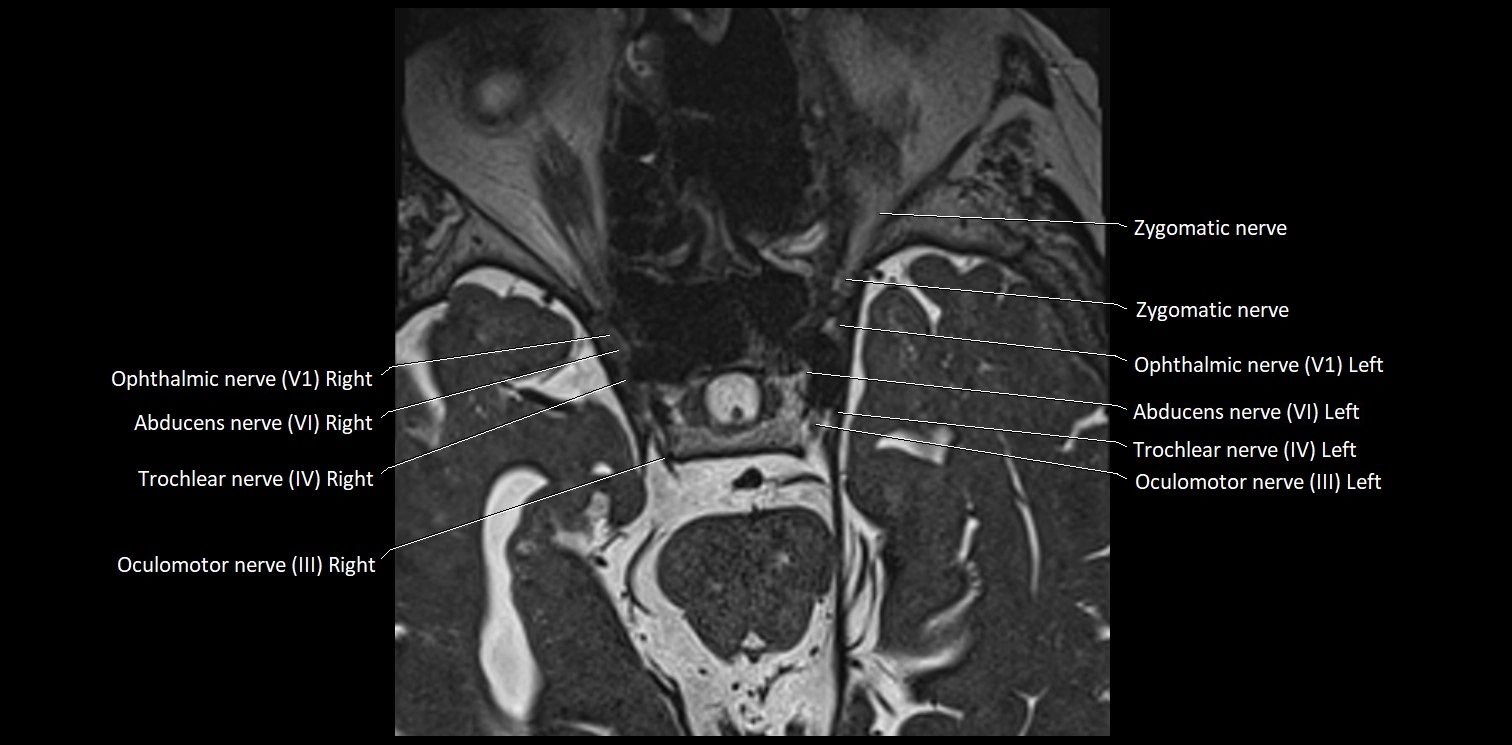

MRI images

image